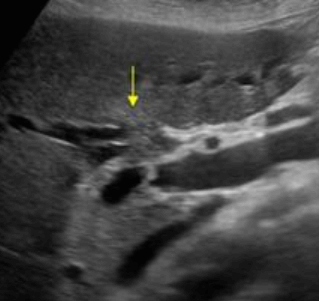

US finding

- 담낭관 또는 담낭 경부에 결석이 확인된다.

- 총간관(CHD) 또는 담낭관(cystic duct)의 확장소견이 보인다.

- 간내외 담관의 확장이 관찰된다.